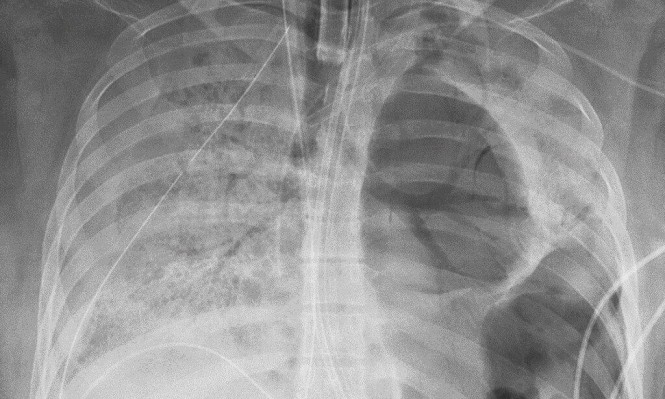

استغرقت العملية عشر ساعات صعبة لأن الفيروس ترك رئتيها مليئتين بالثقوب وانتشر إلى جدار الصدر تقريبا، وفقا للدكتور أنكيت بهارات الذي أجرى العملية أمس الأربعاء.